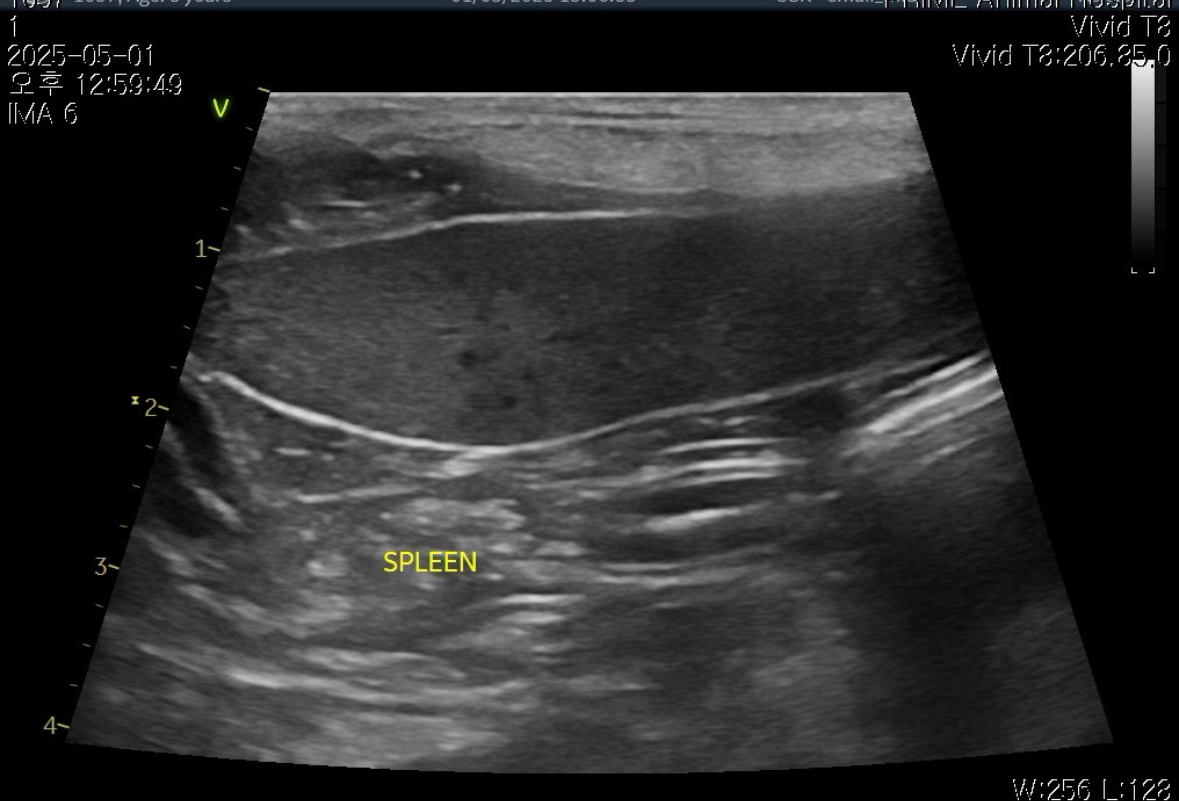

[초음파]